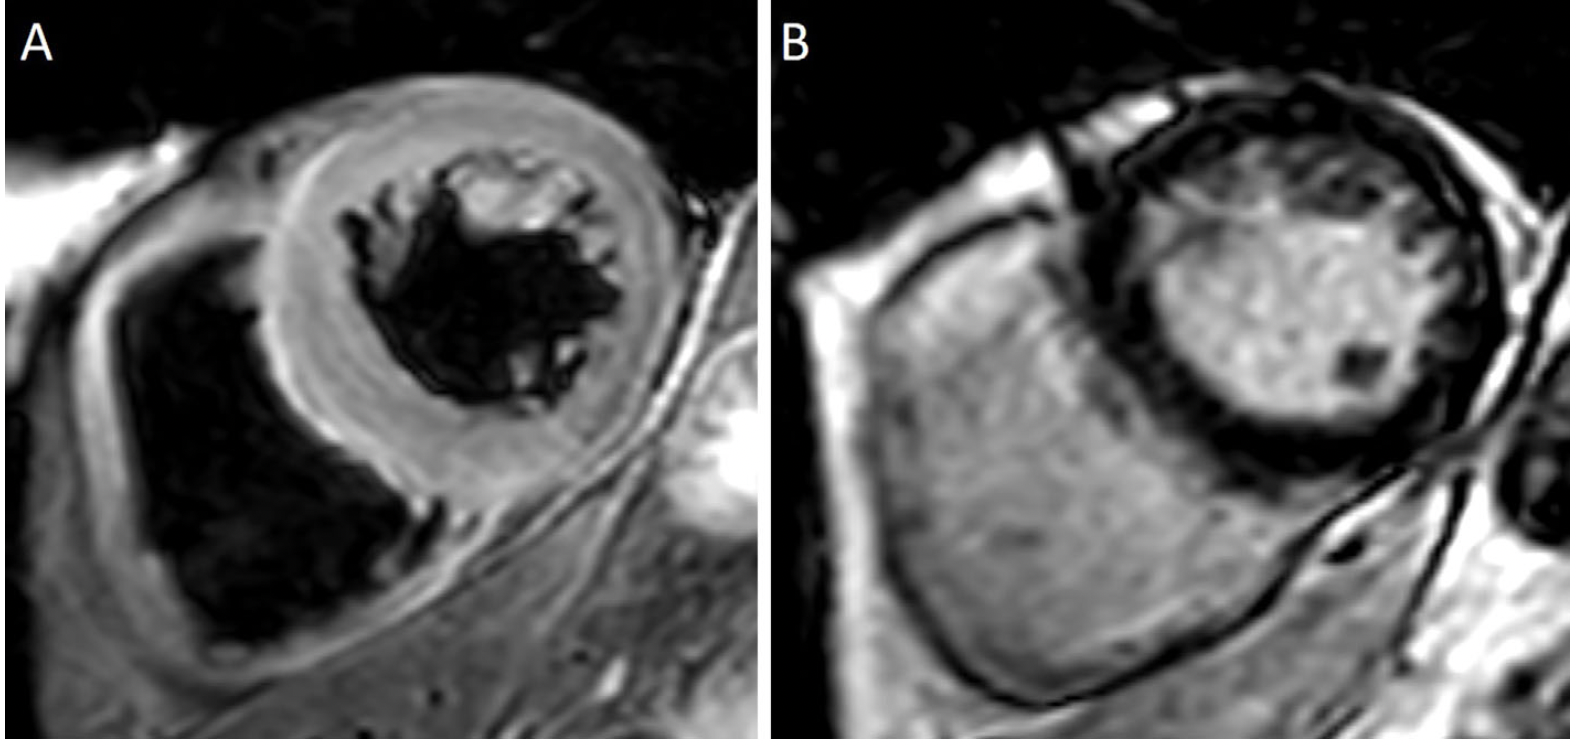

冠状动脉造影显示没有急性冠状动脉综合征的证据(图4)。在计算机断层扫描(第56天)中,肿瘤的原发部位和转移部位均显示显著减少(图1D-F)。在心脏磁共振成像(MRI)(第58天)中,检测到T2信号强度的整体增加(图5A);晚期钆增强显像未发现异常发现(图5B),但确实表明存在心肌水肿,这与急性期心肌炎一致。

图5: 心脏磁共振成像。可见T2信号强度整体升高(A),但晚期钆增强(LGE)影像学表现正常(B),提示心肌水肿